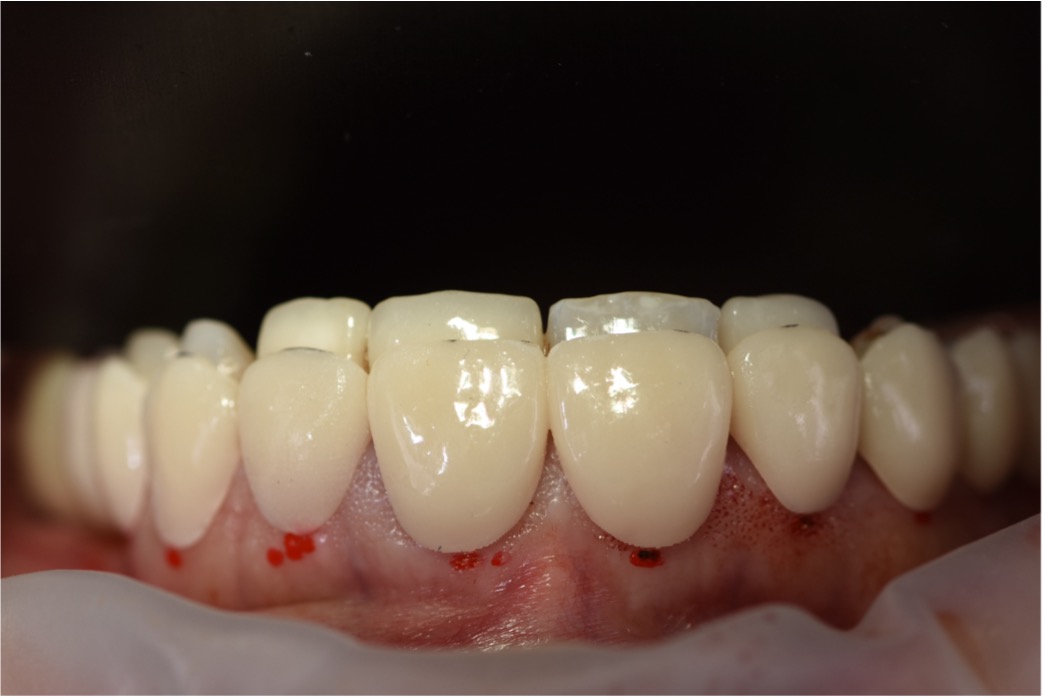

Step 4: Execution of the Final Restorative Plan

The final stage involved tooth preparation and the placement of definitive ceramic restorations. Using SmileFy digital smile design, the restorations were designed to replicate the previously approved mockup and accommodate the new gingival

architecture. These restorations were fabricated with high precision, ensuring excellent fit, esthetics, and durability. The bonding procedure was carried out with attention to Figure 19: 3D Printed Surgical Guide Try In Figure 20: Close Up Difference between 3D Printed Mockup and Initial Teeth Figure 21: During digital crown lengthening Figure 22: Post Op Intraoral Picture detail, followed by polishing to achieve a natural and vibrant finish. The completed smile

was assessed for functionality, esthetics, and the patient’s satisfaction.

Final Outcome

The outcome of the treatment was a significant transformation in the patient's smile. The excessive gingival display was successfully reduced, and the teeth were restored to natural proportions, resulting in a more confident and attractive appearance. The patient expressed a high level of satisfaction and comfort with the result. Final photographs showed harmonious integration between teeth, gums, and facial esthetics. The patient received comprehensive instructions on hygiene and maintenance to ensure the longevity of the results.